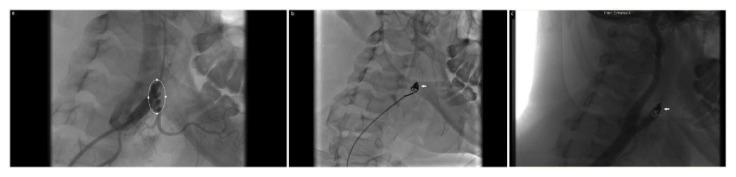

Carotid artery pseudoaneurysms are infrequently encountered in clinical practice. Major contributory etiologies include blunt trauma, infections, cystic medial necrosis, fibromuscular dysplasia, arteriosclerosis, and congenital abnormalities. The authors report an exceedingly rare case of a dissected external carotid artery pseudoaneurysm in a 26-year-old female patient with neurofibromatosis complicated by preeclampsia at 28-week period of gestation, safely and successfully treated by coil embolization.

颈动脉假性动脉瘤在临床实践中并不常见。主要病因包括钝性创伤、感染、囊性中层坏死、纤维肌发育不良、动脉硬化和先天性异常。作者报告了一例极为罕见的病例,一名26岁患有神经纤维瘤病且在妊娠28周时并发先兆子痫的女性患者,出现了颈外动脉夹层假性动脉瘤,通过弹簧圈栓塞术得到了安全、成功的治疗。